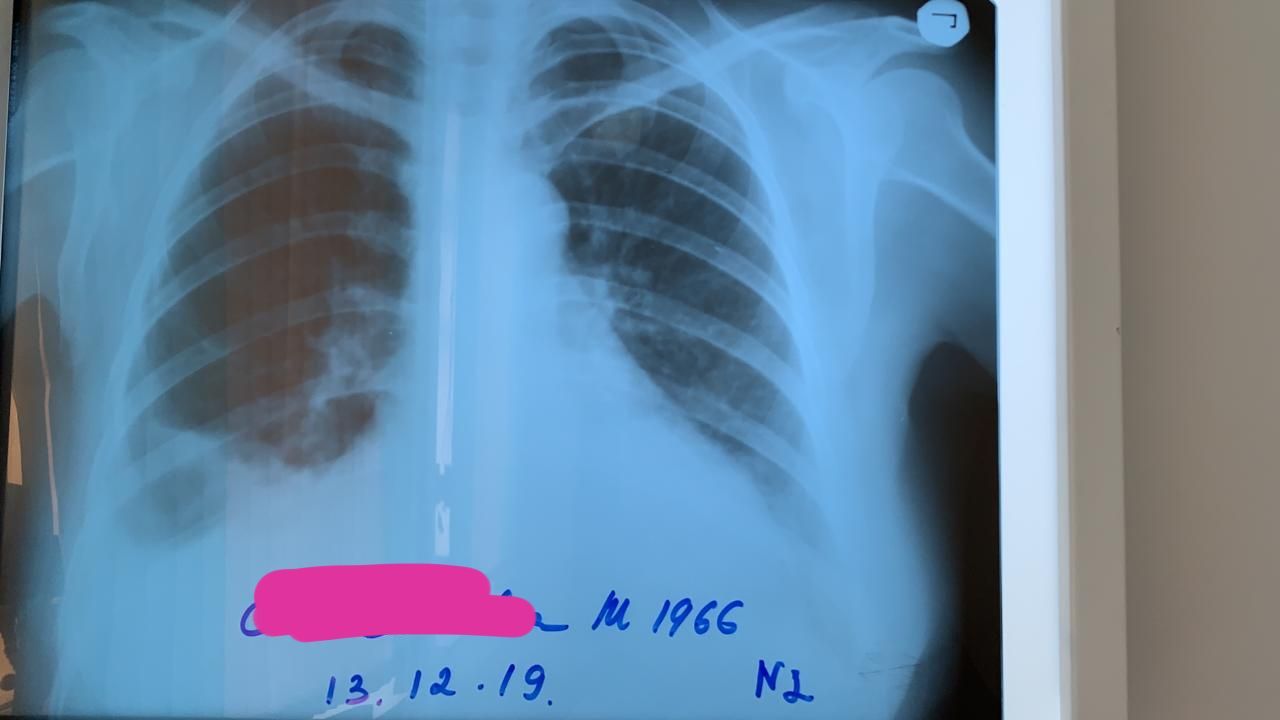

Диагноз кардиомиопатия

Это до пункции